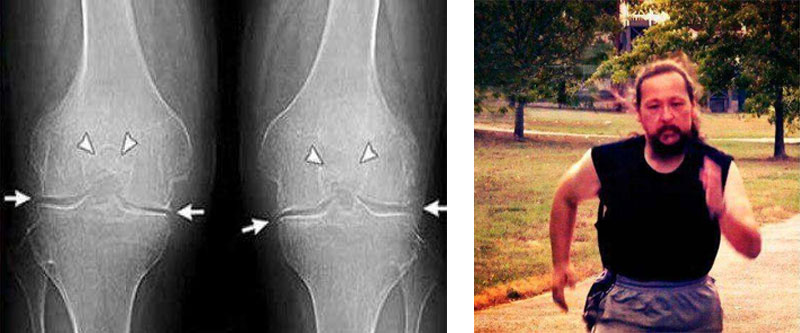

Εμένα το Artroviv Flex+ με βοήθησε πολύ! Πρήστηκε το γόνατο δεν μπορούσα

να λυγίσω

το πόδι μου. Ο πατέρας μου μου έφερε από κάπου το και Artroviv Flex+ Δόξα το Θεό! Δείτε την

διαφορά:

Εμένα το Artroviv Flex+με βοήθησε πολύ! Πρήστηκε το γόνατο δεν μπορούσα να

λυγίσω το

πόδι μου. Ο πατέρας μου μου έφερε από κάπου το και Artroviv Flex+ Δόξα το Θεό! Δείτε την διαφορά:

Εμένα το Artroviv Flex+ με βοήθησε πολύ! Πρήστηκε το γόνατο δεν μπορούσα να λυγίσω το πόδι μου. Ο πατέρας μου μου έφερε από κάπου το και Artroviv Flex+ Δόξα το Θεό! Δείτε την διαφορά: